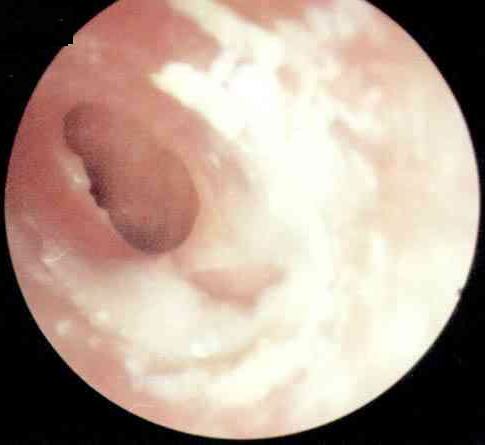

慢性化脓性中耳炎是中耳粘膜、骨膜或深达骨质的慢性化脓性炎症,常与慢性乳突炎合并存在,拖延不治或治疗不当,可引起严重的颅内、外并发症而危及生命。慢性化脓性临床上以耳内反复流脓、鼓膜...[详细]

诊断中耳炎一定要“准”,如果不能够及时发现病情或者把中耳炎错当成其他疾病就麻烦了。因为,中耳炎长时间不得到有效治疗的话引发耳膜穿孔,严重时还会导致失明,必须对其高度重视。中耳炎的...[详细]